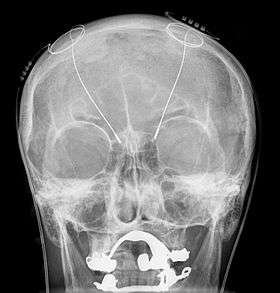

All three components are surgically implanted inside the body. Lead implantation may take place under local anesthesia or with the patient under general anesthesia ("asleep DBS") such as for dystonia. A hole about 14 mm in diameter is drilled in the skull and the probe electrode is inserted stereotactically. During the awake procedure with local anesthesia, feedback from the patient is used to determine optimal placement of the permanent electrode. During the asleep procedure, intraoperative MRI guidance is used for direct visualization of brain tissue and device.[15] The installation of the IPG and extension leads occurs under general anesthesia.[16] The right side of the brain is stimulated to address symptoms on the left side of the body and vice versa.

Because the brain can shift slightly during surgery, there is the possibility that the electrodes can become displaced or dislodged from the specific location. This may cause more profound complications such as personality changes, but electrode misplacement is relatively easy to identify using CT. There may also be complications of surgery, such as bleeding within the brain. After surgery, swelling of the brain tissue, mild disorientation, and sleepiness are normal. After 2–4 weeks, there is a follow-up to remove sutures, turn on the neurostimulator, and program it.